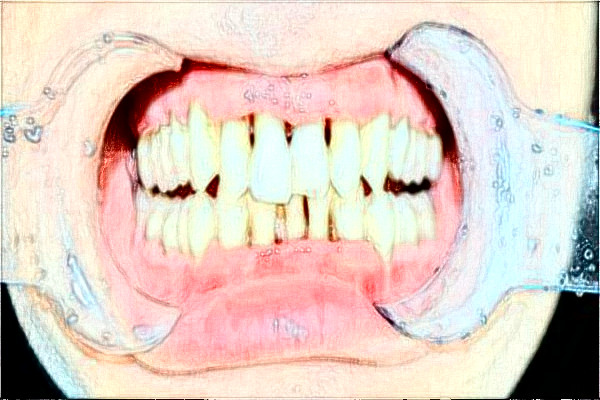

2024九江市第一醫(yī)院正畸案例